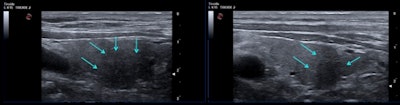

Bearing in mind such behavior of classic subacute thyroiditis, she said she did not find it surprising that hypoechoic areas of atypical thyroiditis related to COVID-19 also persisted after two to three months. Furthermore, the whole thyroid gland was a little more dishomogeneous and showed a diffusely hypoechoic pattern compared to a normal thyroid, although she said it was quite difficult to standardize in the ultrasound machine settings.

Muller and colleagues started a surveillance program to monitor the thyroid function of patients every three months after being hospitalized for moderate to severe COVID-19 disease. The patients undergo routine blood and ultrasound testing using a MyLab 25Gold ultrasound scanner from Esaote to monitor their thyroid function and signs of inflammation.

A total of 53 patients (60% men, mean age 61 ± 10 years) have so far completed the evaluation at three months. All of them had normalized thyroid function, but the team found the thyroiditis in people with moderate to severe COVID-19 disease differs from typical thyroiditis in several ways. These include the absence of neck pain, the presence of mild thyroid dysfunction, higher frequency among men, and the association with severe COVID-19 disease.

One-third of the study participants still had signs of thyroid inflammation after three months, even though their thyroid function had normalized. The study is following patients to determine whether this inflammation will trigger permanent thyroid dysfunction or autoimmunity.